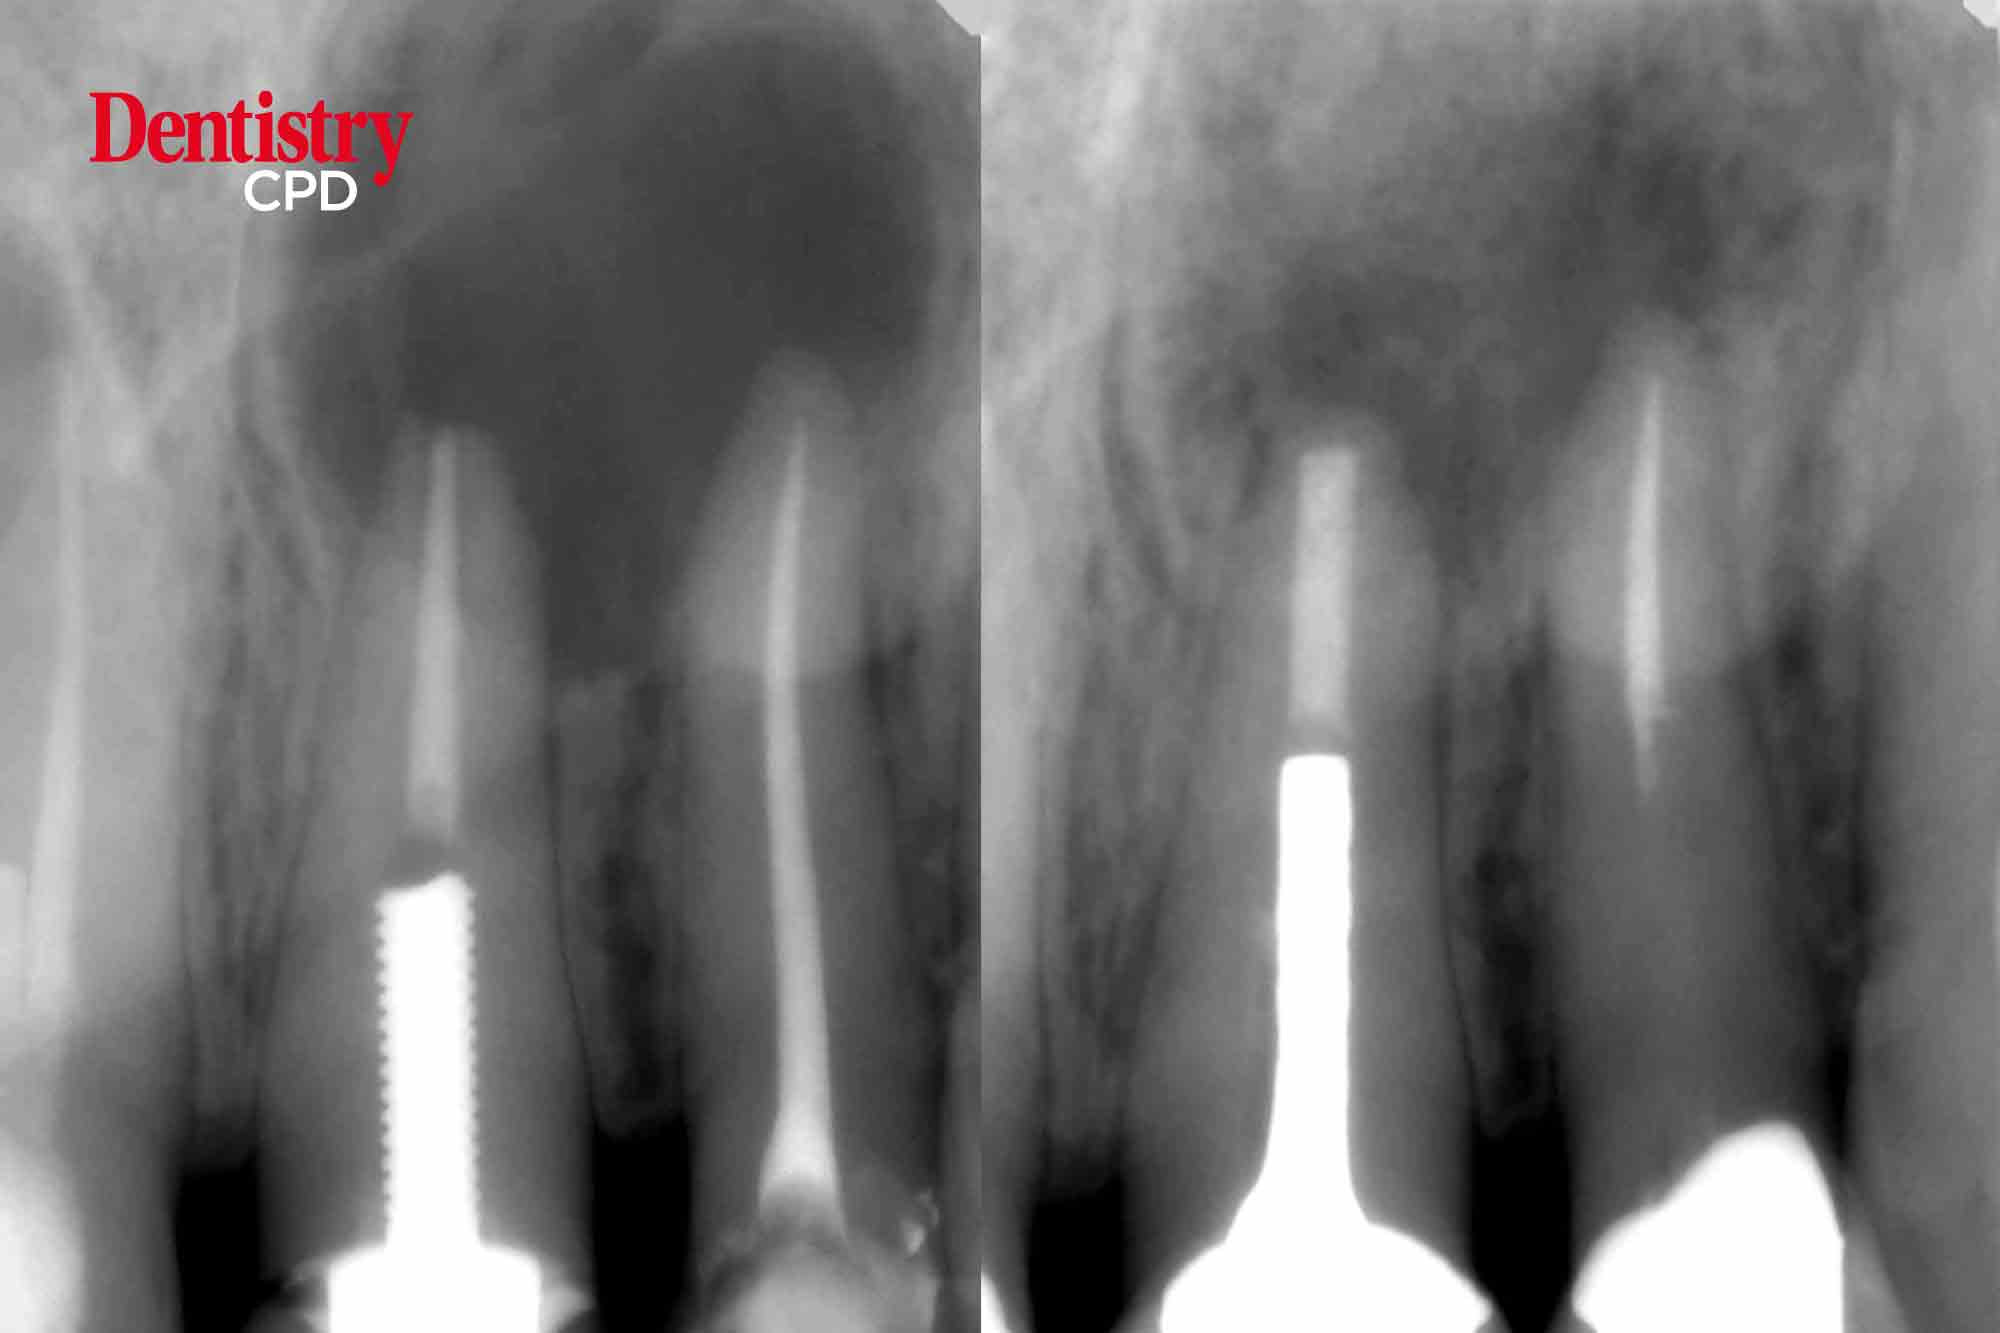

Jason Bedford shows how a new hydroxyapatite root repair material benefits the apical closure and healing of a large peri-radicular radiolucency

To show how a new hydroxyapatite root repair material benefits the apical closure and healing of a large peri-radicular radiolucency.